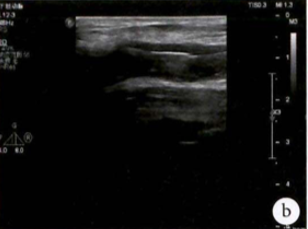

术前超声评估:提示腘动脉血栓。

图:胫腓干血栓及直径

胫后及腓动脉起始处彩色血流图